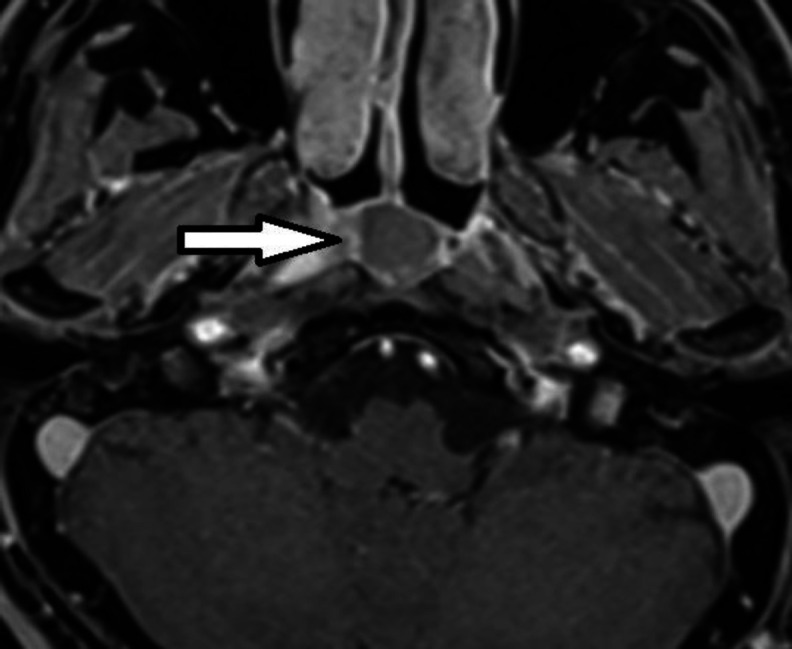

简介大多数鼻咽囊肿无症状且罕见。然而,这些病变很少在常规内窥镜检查和造影检查中被发现。上鼻咽 Thornwaldt 囊肿是一种先天性粘膜良性囊肿。甚至更少见的是,它们会引起不明原因的鼻窦症状,如鼻出血、视力问题和鼻腔堵塞:病例报告:我们在此报告了一例冠状病毒感染后新发听力损失的病例,其影像学检查显示鼻咽部肿块:结论:感染冠状病毒-19 后,我们应考虑高危患者的腮腺囊肿和 Thornwaldt 囊肿。结论:感染科维-19 病毒后,我们应考虑高危患者的腮腺囊肿和 Thornwaldt 囊肿,另一方面,科维-19 病毒感染后的渐进性听力损失也可能是这类囊肿激活所致。

Case report: Here, we report a case with new-onset hearing loss after the coronavirus infection, in which his imaging investigation showed a nasopharyngeal mass.